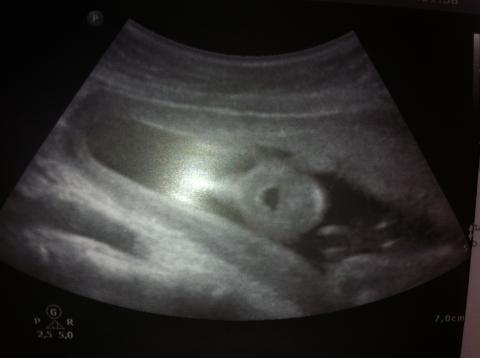

Otevřená pusinka na UZ

Pro větší náhled klikněte na obrázek

Doxuska - 28.11.2013 12:03:51 Dobrý den, je mi 20let, 20+6tt, byla jsem dnes v rámci genetického vyš. na ultrazvuku. Nejprve paní doktorka chválila, říkala jak je vše v normě a jak má být, ale potom si všimla, že miminko má po celou dobu vyšetření otevřenou pusinku. Prý to není normální a jsme objednáni za týden na další kontrolu. Nikde jsem nemohla najít co by to mohlo znamenat, nebo z jakého důvodu? Můžete mi poradit co by mohlo být špatně? Testy na DS vyšly negativní. Přikládám foto. Děkuji za Váš názor.

Miminko bežne otvára a zatvára ústočká, ale nestretla som sa za 11 rokov praxe, že by počas celého UZ vyšetrenia malo len otvorenú pusinku a nehýbal s ňou.